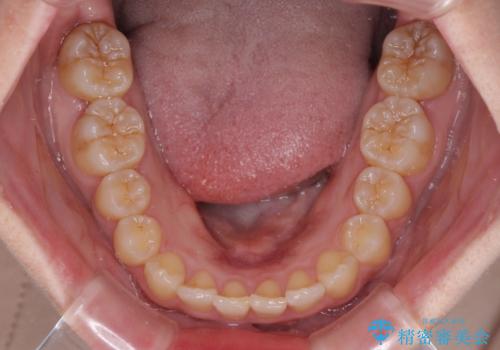

- 前歯のデコボコと奥歯の不正咬合を気にして来院された患者様です。

左右の大臼歯が全て鋏状咬合(シザーズバイト)になっており、治療が難航することが予想されましたが、インビザラインにより治療を行うこととしました。

最難関と思われたシザーズバイトは比較的短期間で解消されました。

しかし、治療中に2度の出産を経験され、治療期間は長くなってしまいましたが、咬みやすく、清掃しやすい歯列を獲得することができました。